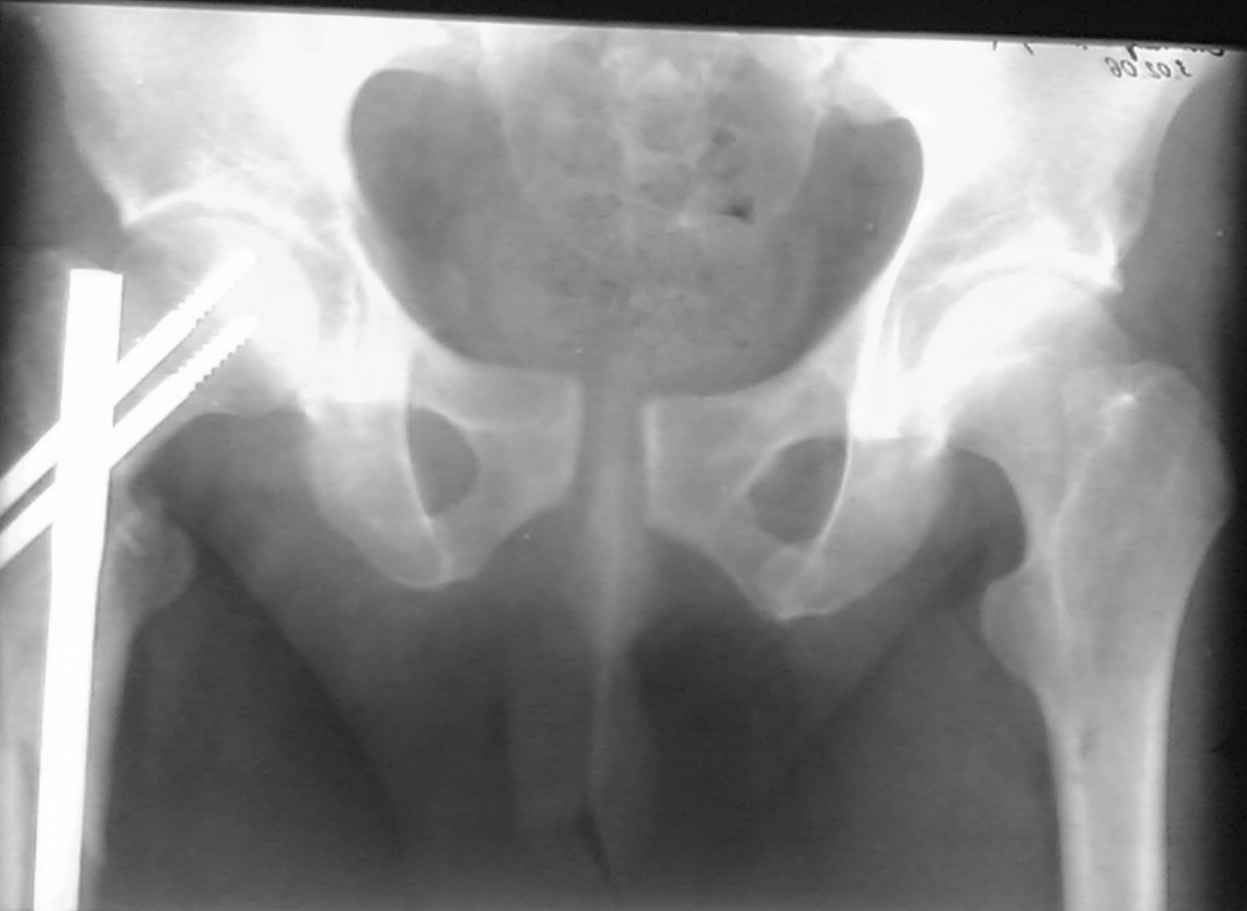

извините за опоздание , вот фотографии

Репозиция действительно очень неплохая, но чтобы уменьшить риск развития поздней нестабильности, в такой ситуации лучше выполнить синтез лонного сочленения пластиной и оставить аппарат месяца на 2.

<На R-мме таза ( в прямой проекции, вход и выход из таза) определяется изолированный разрыв лонного сочленения с диастазом 4см,расширение щели правого КПС(вертикальной нестабильности нет, >

Разрыв лонного сочленения с диастазом более 2,5 см говорит о полном разрыве крестцово-подвздошного сочленения (вертикальная нестабильность) или двустороннем характере повреждения (к/п с обеих сторон)

Если повреждение одностороннее - необходима фиксация задних отделов (винт или аппарат)

Если двусторолннее ротационное - можно оставить в передней раме.

Необходимость открытой репозиции и внутренней фиксации определяется площадью ПЛОТНОГО контакта лонных костей, если она меньше 2/3 лучше не ждать

3 месяцев.

Даже если контакт идеальный синтез пластиной

поможет уменьшить риск хр. неестабильности (особенно если пациент тучный, а аппарат ненадежный), быстрее снять аппарат, быстрее активизируется.

В представленном случае повреждение несомненно ротационное и реальный диастаз как раз около пограничных 2,5 см, репозиция идеальная, достигнута в первые дни после травмы. Я бы ограничился 3 мес фиксации в аппарате с ограничением нагрузки первый месяц, и функциональными снимками в 6 -8 недель.

ПЕРЕСМАТРИВАЛ РАЗНЫЕ СНИМКИ И НАШЕЛ НА ЭТУ ТЕМУ ФОРУМА СНИМОК. БОЛЬНОЙ БЫЛ ПРООПЕРИРОВАН НА ПРАВОЕ БЕДРО ПОСЛЕ ЧЕГО СДЕЛАН ТАЗ В ЦЕЛОМ. ВОТ ЧТО НАШЛОСЬ.

КАКОЕ ВАШЕ МНЕНИЕ О ТАКТИКЕ.

ДУМАЮ ПРОШЛО ОКОЛО 10 ДНЕЙ.